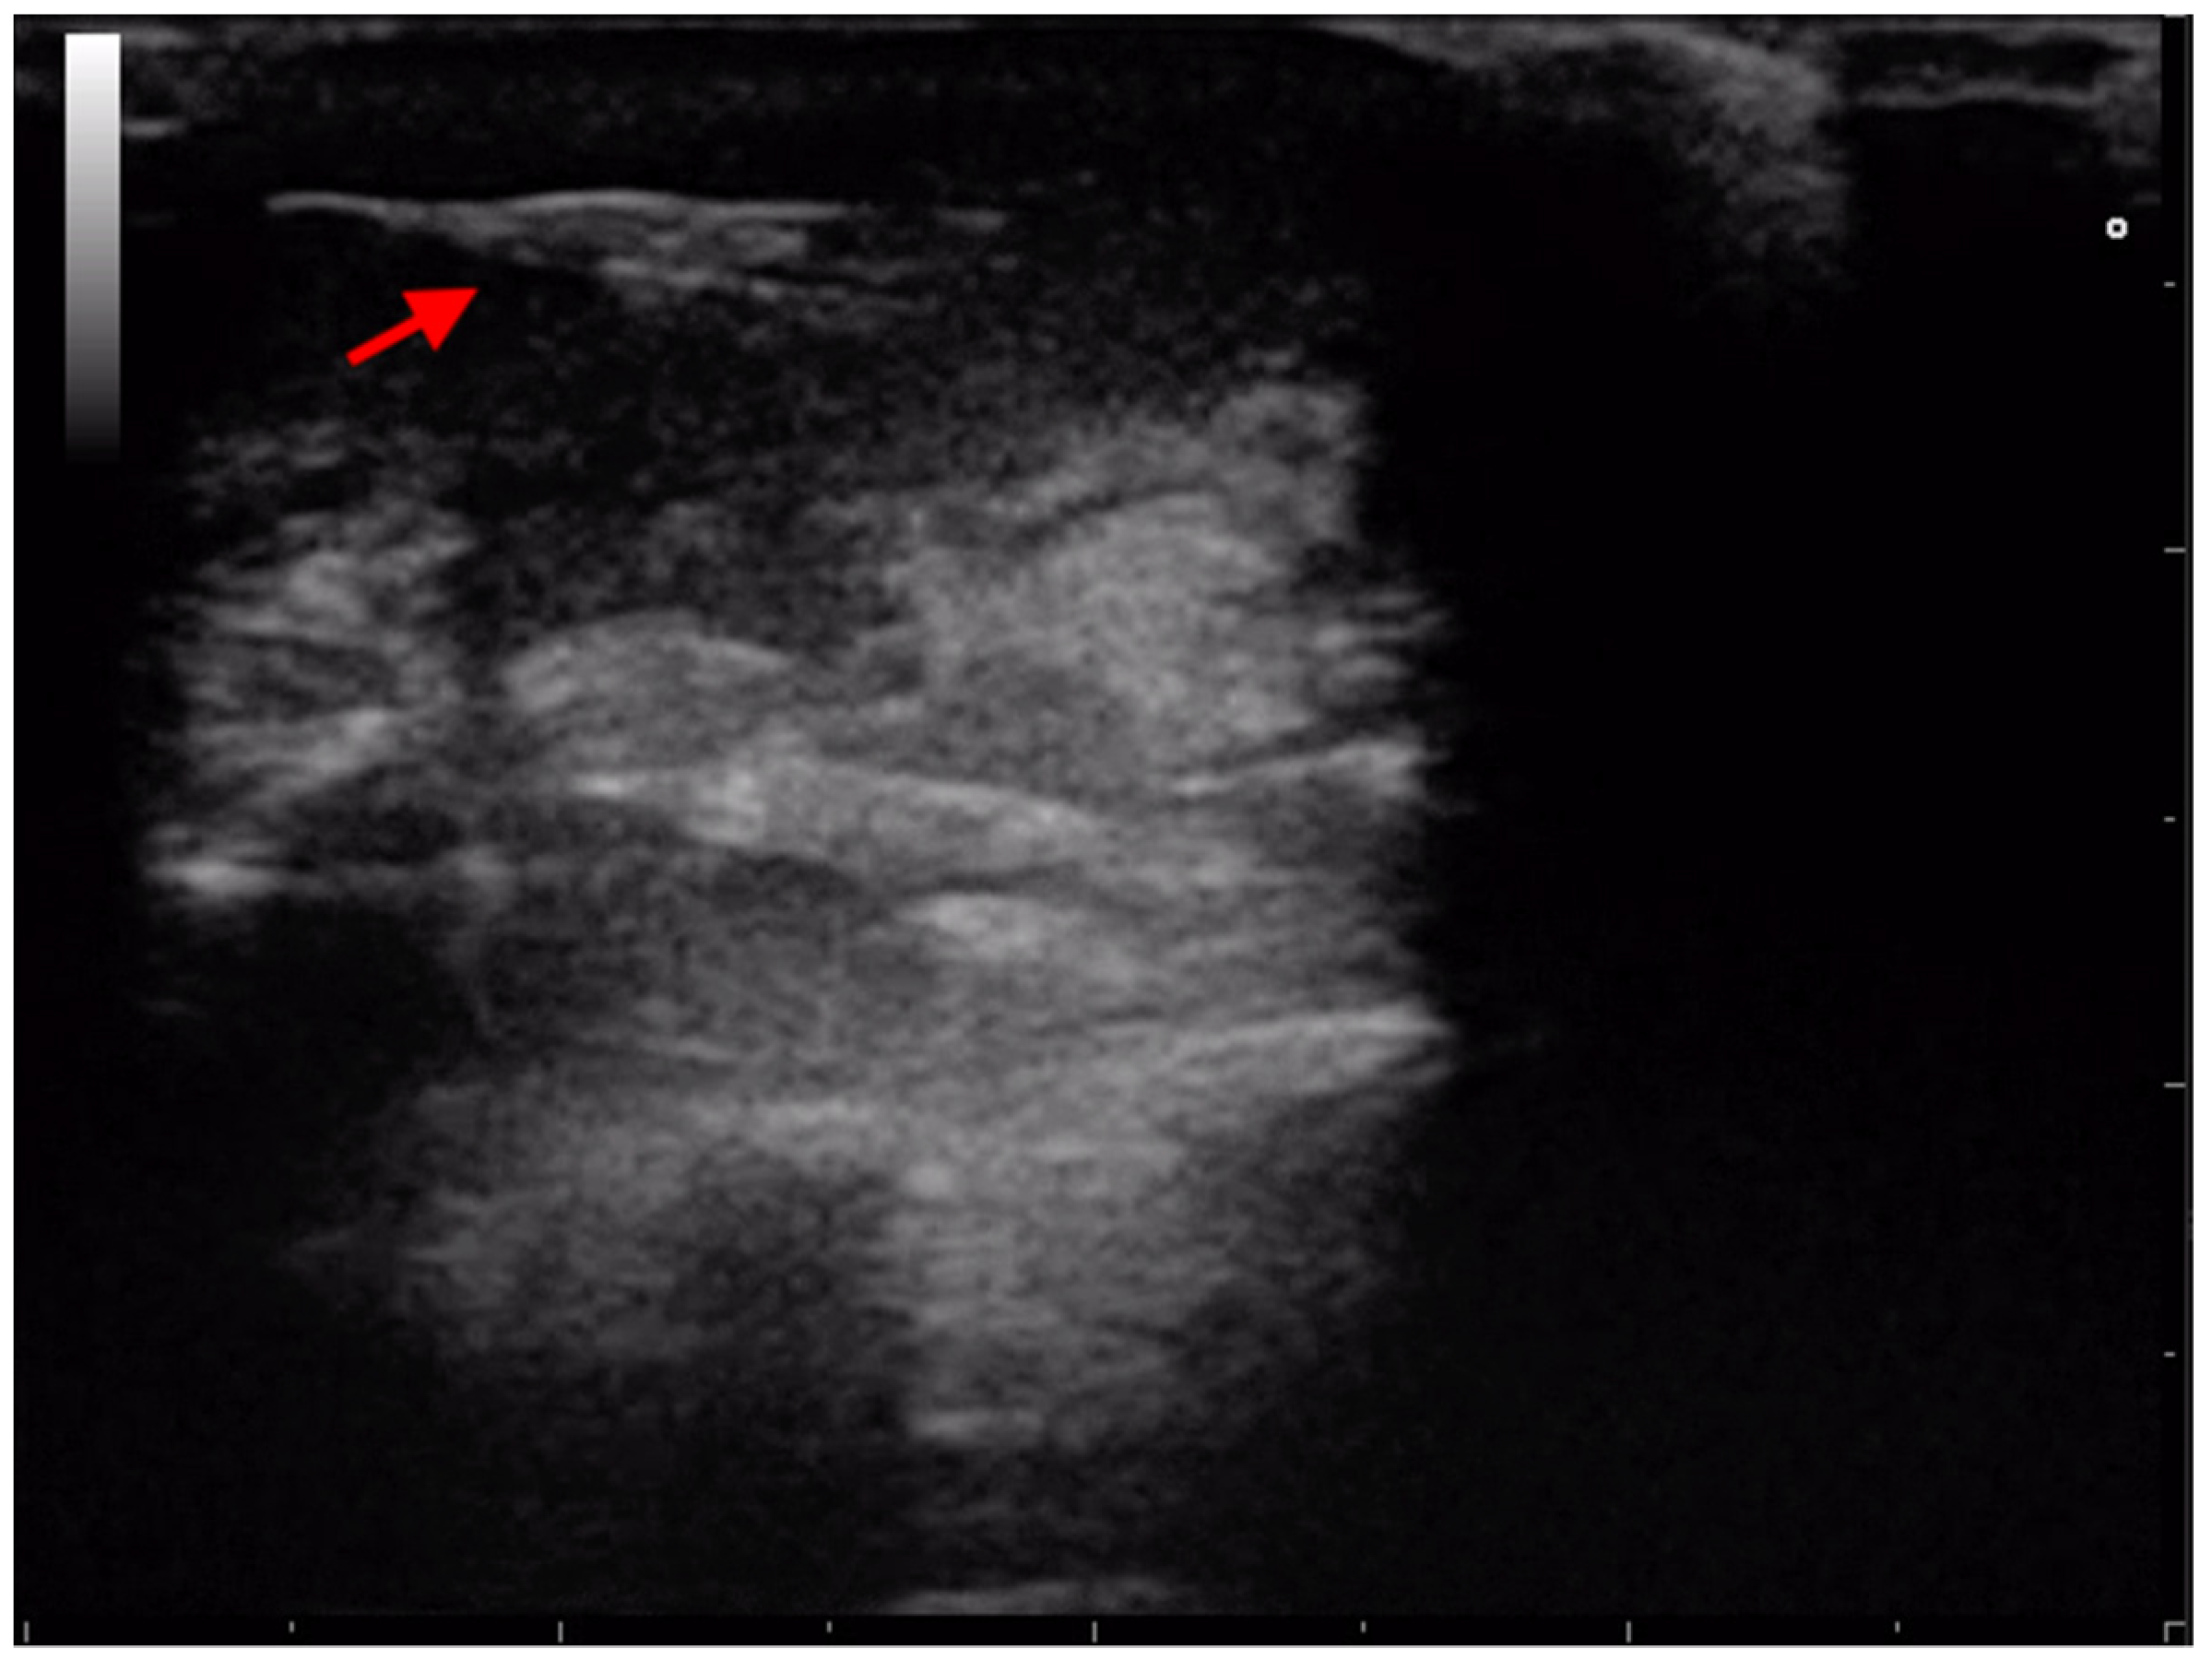

3.2. Retroperitoneal Migration